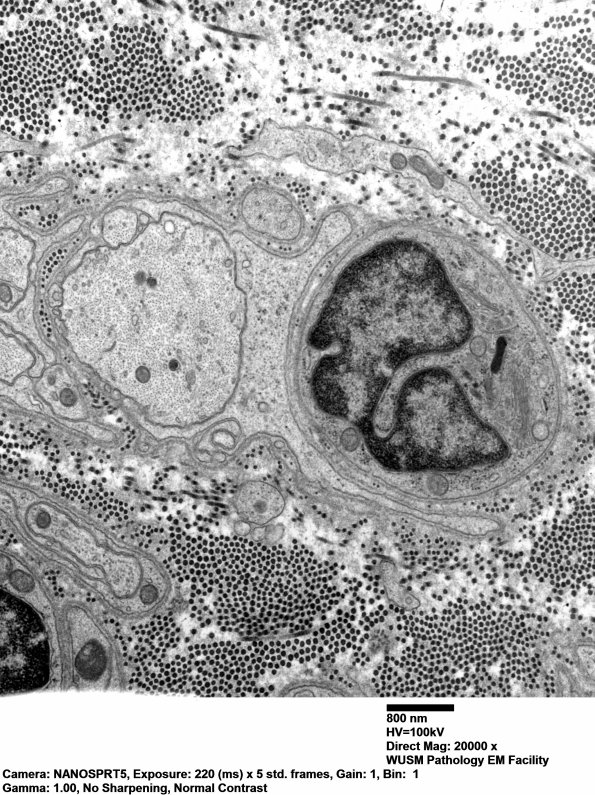

3B1,2 A large demyelinated axon shows a prominent cytoskeleton. Electron microscopy shows no evidence of macrophage-mediated demyelination (i.e., no definitive pathognomonic correlate of Guillain-Barre syndrome) (electron micrographs)